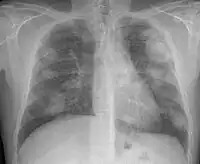

There are three key elements to the diagnosis of silicosis. First, the patient history should reveal exposure to sufficient silica dust to cause this illness. Second, chest imaging (usually chest x-ray) that reveals findings consistent with silicosis. Third, there are no underlying illnesses that are more likely to be causing the abnormalities. Physical examination is usually unremarkable unless there is complicated disease. The examination findings are not specific for silicosis.[19]

For uncomplicated silicosis, chest x-ray will confirm the presence of small (< 10 mm) nodules in the lungs, especially in the upper lung zones. Using the ILO classification system, these are of profusion 1/0 or greater and shape/size "p", "q", or "r". Lung zone involvement and profusion increases with disease progression. In advanced cases of silicosis, large opacity (> 1 cm) occurs from coalescence of small opacities, particularly in the upper lung zones.

With retraction of the lung tissue, there is compensatory emphysema. Enlargement of the hilum is common with chronic and accelerated silicosis. In about 5–10% of cases, the nodes will calcify circumferentially, producing so-called "eggshell" calcification. This finding is not pathognomonic (diagnostic) of silicosis. In some cases, the pulmonary nodules may also become calcified.

Silicosis that develops 5–10 years after first exposure to higher concentrations of silica dust. Symptoms and x-ray findings are similar to chronic simple silicosis, but occur earlier and tend to progress more rapidly. Patients with accelerated silicosis are at greater risk for complicated disease, including progressive massive fibrosis (PMF).

Silicosis can become "complicated" by the development of severe scarring (progressive massive fibrosis, or also known as conglomerate silicosis), where the small nodules gradually become confluent, reaching a size of 1 cm or greater. PMF is associated with more severe symptoms and respiratory impairment than simple disease. Silicosis can also be complicated by other lung disease, such as tuberculosis, non-tuberculous mycobacterial infection, and fungal infection, certain autoimmune diseases, and lung cancer. Complicated silicosis is more common with accelerated silicosis than with the chronic variety.